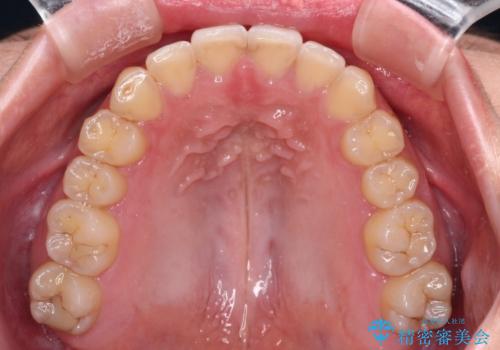

- 食いしばりが気になっていたとのことで来院された患者様です。

当初は睡眠時のマウスピースのみの製作をご希望でしたが、矯正治療の提案をしたところ、インビザラインにて矯正治療を行うこととなりました。

矯正治療中に食いしばりがより強くなることがあるため、半年に1回のペースでボツリヌストキシンによる咬合力緩和を並行して行うこととしました。

咬合力の緩和と食いしばりがちな咬み合わせが改善され、顎の負担が大幅に軽減されました。